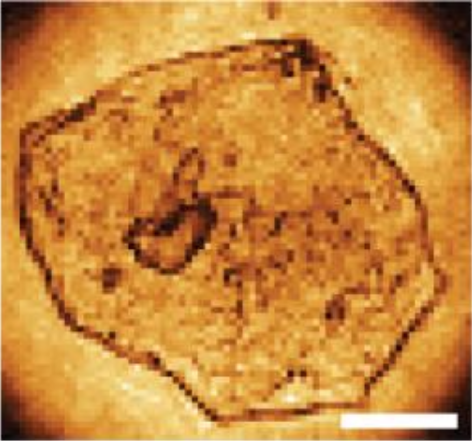

Laforest T., Künzi M., Kowalczuk L., Carpentras D., Behar-Cohen F. and Moser C. , Transscleral optical phase imaging of the human retina, Nature Photonics, March 2020. |